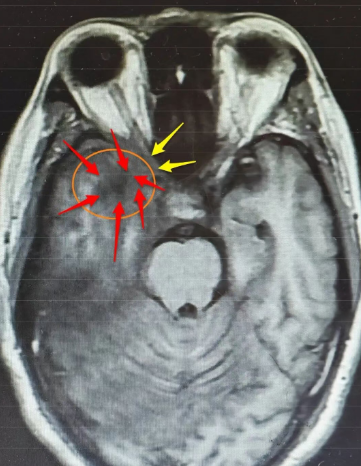

入院后,神经外科王典春主任为他完善了相关检查,对比院外之前的检查结果,发现他的右侧颞叶病变较前明显扩大,长径已达54mm,且顶叶、枕叶发展,邻近脑膜增厚明显,“从影像学表现及实验室检查看,炎性病变可能性不大,再结合患者症状进行性加重的特点,胶质瘤也不能排除。”王典春主任在病例讨论中强调,右侧颞叶的占位性病变已压迫视神经,这正是导致李先生右眼失明的关键原因,若不及时干预,不仅视力恢复无望,病变还可能进一步侵犯脑组织,威胁生命安全。

在麻醉团队的密切配合下,王典春主任凭借丰富的临床经验与精湛的操作技巧,小心翼翼地通过右侧翼点入路进入颅内,精准定位右侧颞叶病变区域,在保护周围正常脑组织与神经的前提下,成功切除部分病变组织送检,同时王主任还对受压的右侧视神经进行了细致减压,手术过程顺利。

最终术后病理报告也证实了李先生真正的病因是右侧颞顶枕叶的节细胞胶质瘤(WHO1级),这一结果为后续治疗提供了明确方向,神经外科专家团队将根据李先生手术后的恢复状况,联合肿瘤科等多个相关科室共同为他制定个性化的综合治疗方案,进一步控制病情发展。